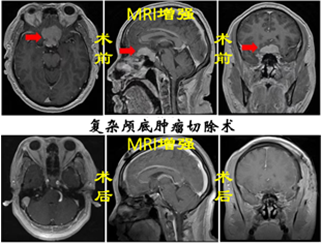

神經(jīng)腫瘤:神經(jīng)腫瘤作為神經(jīng)系統(tǒng)疾病中最為棘手的疾病之一,常見的有膠質瘤、腦膜瘤、垂體瘤、神經(jīng)鞘瘤、轉移瘤、先天性腫瘤等,手術方式包括超聲導航+熒光造影引導下腦腫瘤切除術、鞍結節(jié)腦膜瘤切除術等,借助顯微鏡等先進設備,在保留正常腦組織的情況下,最大程度切除腫瘤組織,為患者爭取后續(xù)康復機會。